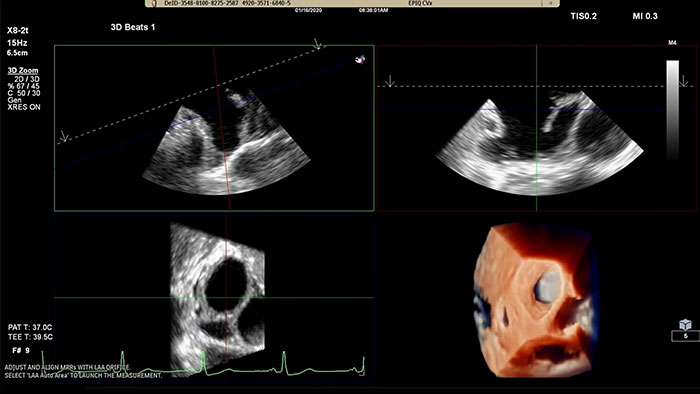

EPIQ CVx – TrueVue Glass mit 3D Auto LAA

Schnelle Durchführung von Messungen am Ostium des linken Vorhofohrs in herkömmlicher Darstellung oder in TrueVue Glass Darstellung mit 3D Auto LAA

• Schnelle, reproduzierbare Darstellung der Morphologie des linken Vorhofohrs und automatische Messung des Ostiums ausschließlich mit Ultraschall